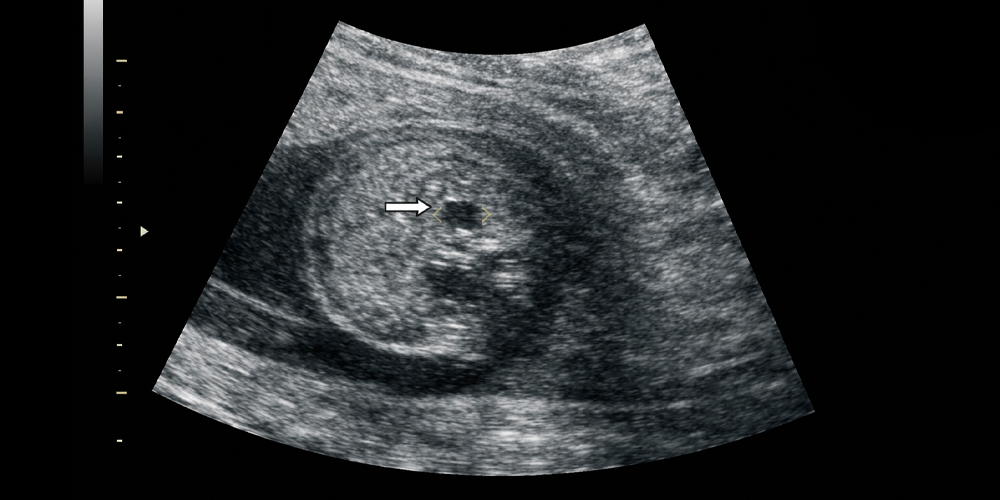

Böbreklerin iç boşluklarında genişleme (Pelvikaliektazi, piyelektazi)